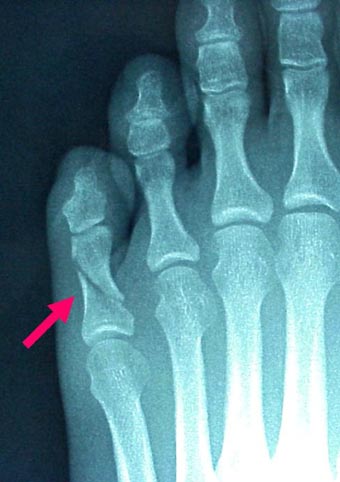

骨折・脱臼の治療について

当院は、骨折・脱臼の応急処置専門接骨院です。